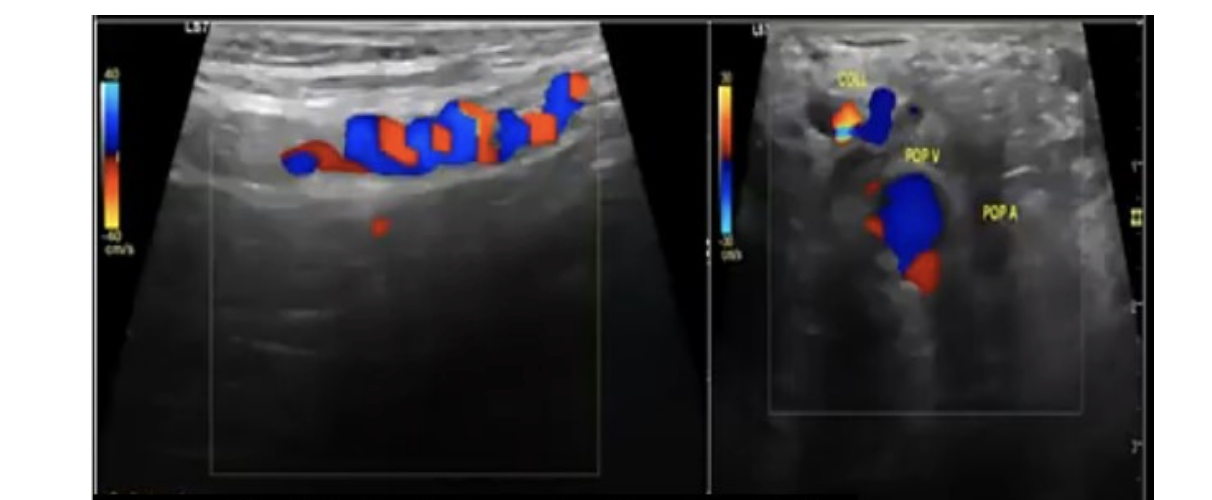

a 30 yo male has persistent right calf pain w/exercise. this is the right popliteal artery w/foot in neutral + flexed position

.

a) Buerger disease

b) anterior compartment syndrome

c) popliteal entrapment

d) Leriche syndrome